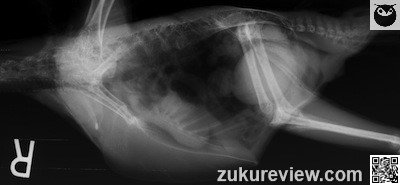

A 21-year-old scarlet macaw is presented with polydipsia, watery droppings and inappetence. On examination, the bird was fluffed and depressed with minimal pectoral muscle atrophy. The crop was fluctuant.

Which one of the following choices is the most likely diagnosis?